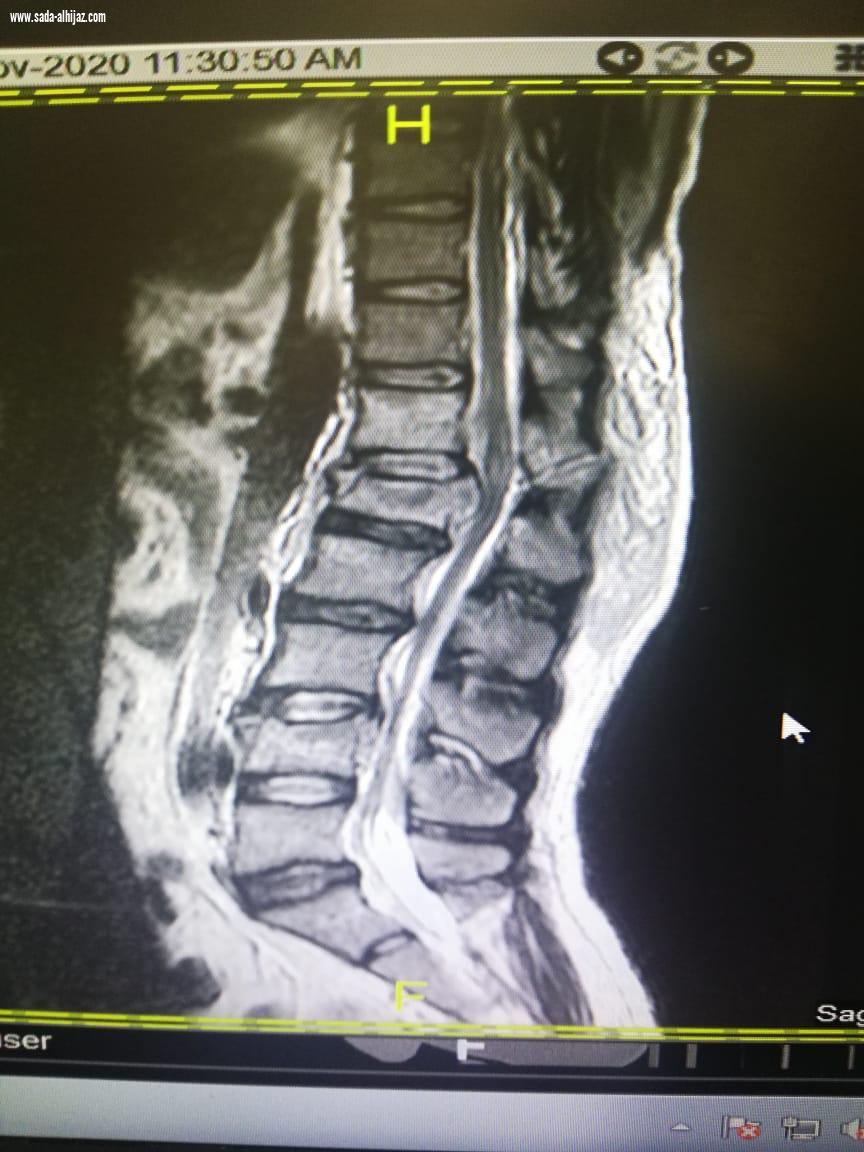

عبدالعزيزالنفيعي- الطائف تمكن فريق طبي بمستشفى الملك عبدالعزيز عضو التجمع الصحي بمكة بقسم جراحة المخ والأعصاب من إنقاذ حياة رجل يبلغ من العمر ( 30) تعرض لسقوط من الدور الخامس من إحدى البنايات بالعاصمة المقدسة . واوضح رئيس قسم جراحة المخ والاعصاب الدكتور زهير برناوي ان المصاب حضر إلى قسم الطوارئ بالمستشفى وهو يعاني من كسر مضاعف بالفقرة القطنية الاولى وكسر منضغط بالفقرة القطنية الرابعة وانزلاق غضروفي حاد بين الفقرتين الثانية والثالثة القطنية ونتج عن ذلك شلل نصفي وعدم التحكم بالإخراج وبعد عمل الاشعات والفحوصات اللازمة وعلى إثره دخل إلى غرفة العمليات، كحاله طارئة وتم اجراء عملية تثبيت للفقرات من الناحية الصدريه رقم ١١ وحتى العجزية رقم ١ مروراً بكل الفقرات القطنية الخمسة مع استئصال الغضروفي استغرقت العملية ( 8 ) ساعات وتم تنويم المصاب بالعناية المركزة لمدة يومين بقيادة استشاري جراحة المخ والاعصاب الدكتور محمد مرسي المشد وبفضل من الله تكللت العملية - بالنجاح، حيث تم نقل المصاب إلى قسم التنويم وخضع لعلاج دوائي وطبيعي الى ان استطاع السير على قدمية وهو بحالة مستقرة وتم خروجه من المستشفى.